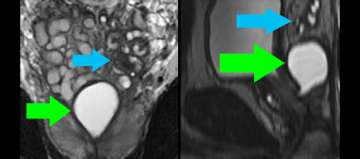

8) Benign Disease (Infertility)

- Young man presents with infertility (azospermia)

- Workup and medical history otherwise noncontributory

- Muellerian duct remnant in central upper prostate may obstruct ejaculatory ducts

- Left seminal vesicles are atrophic